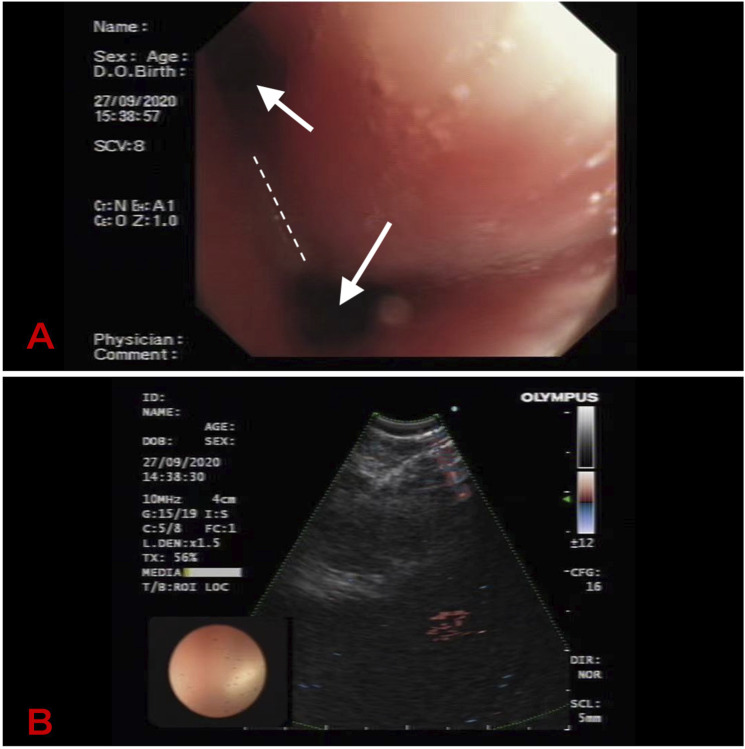

本研究报告了一例小细胞肺癌并发复发性多软骨炎的临床资料。我们报告一例57岁女性,表现为咳嗽、咳痰和发烧。在医院进行的计算机断层扫描显示双肺支气管壁弥漫性增厚。支气管镜检查显示气管黏膜增厚、变窄、塌陷,支气管镜可通过。两侧支气管黏膜增厚水肿,表面粗糙,各支气管狭窄,椎脊增宽。针活检:结合免疫组化结果考虑小细胞癌。经抗感染治疗后症状未见改善。住院期间左耳廓红肿,耳廓塌陷,左眼结膜下出血,无明显原因。经多学科会诊,考虑肺小细胞肺癌cT0N2Mx瘤胃淋巴结转移及RP。治疗:强的松,口服治疗RP。小细胞肺癌采用化疗与放疗联合治疗。化疗方案为卡铂联合依托泊苷。患者接受放化疗后已随访1年;目前病人的病情稳定。结合我们患者的病例,对于出现耳廓软骨炎、眼部炎性疾病、鼻软骨炎等症状的RP,我们要特别注意该病例是否由肺癌合并复发性多软骨炎引起。由于本病罕见,临床医师应提高对本病的认识,争取早期诊断和治疗。

The present study reports the clinical data of a patient with small cell lung cancer who developed relapsing polychondritis. We report a case of a 57-year-old female presented with cough, expectoration, and fever. A Computed Tomography (CT) scan performed at the hospital revealed diffuse thickening of bronchial walls in both lungs. Bronchoscopy revealed that the tracheal mucosa was thickened, narrowed, and collapsed, and the bronchoscope could pass through. The bronchial mucosa on both sides was thickened and edematous, the surface was rough, each bronchus was narrow, and the intervertebral ridges were widened. Needle biopsy: considering small cell carcinoma in combination with immunohistochemical results. Her symptom was not improved after anti-infective therapy. The left auricle was red and swollen, the auricle collapsed, and the left eye had subconjunctival hemorrhage during her hospitalization without obvious cause. After multidisciplinary consultation, pulmonary small cell lung cancer cT0N2Mx rumen lymph node metastasis and RP were considered. Treatment: Prednisone, orally for RP. Chemotherapy combined with radiotherapy was given for small cell lung cancer. The chemotherapy regimen was carboplatin combined with etoposide. The patient has already been followed for 1 year after receiving chemoradiotherapy; the condition of the patient is stable at present. Based on the case of our patient, for cases of RP with symptoms such as auricle chondritis, ocular inflammatory disease, and nasal chondritis, we should pay great attention to whether the case is caused by lung cancer with relapsing polychondritis. Because of the rarity of the disease, the clinician should improve the recognition of the disease in order to strive for early diagnosis and therapy.